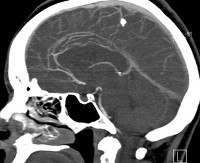

CT of brain vessels.

КТ сосудов головного мозга. Ангиографическое исследование структуры внутричерепной ткани, состояния артериального и венозного кровотока с реконструкцией компьютерных данных. Тест проводится с внутривенным введением рентгеноконтрастного материала. В процессе КТ-ангиографии снимки снимаются послойно, на основе которых выполняется компьютерная реконструкция сосудистой сети головного мозга. Архитектура сосудов головного мозга оценивается по их контурам, состоянию света, разветвленности и однородности контраста. КТ позволяет обнаружить артериовенозные мальформации, аневризмы, стенозы, сгустки, атеросклеротические поражения внутричерепного сосудистого русла.